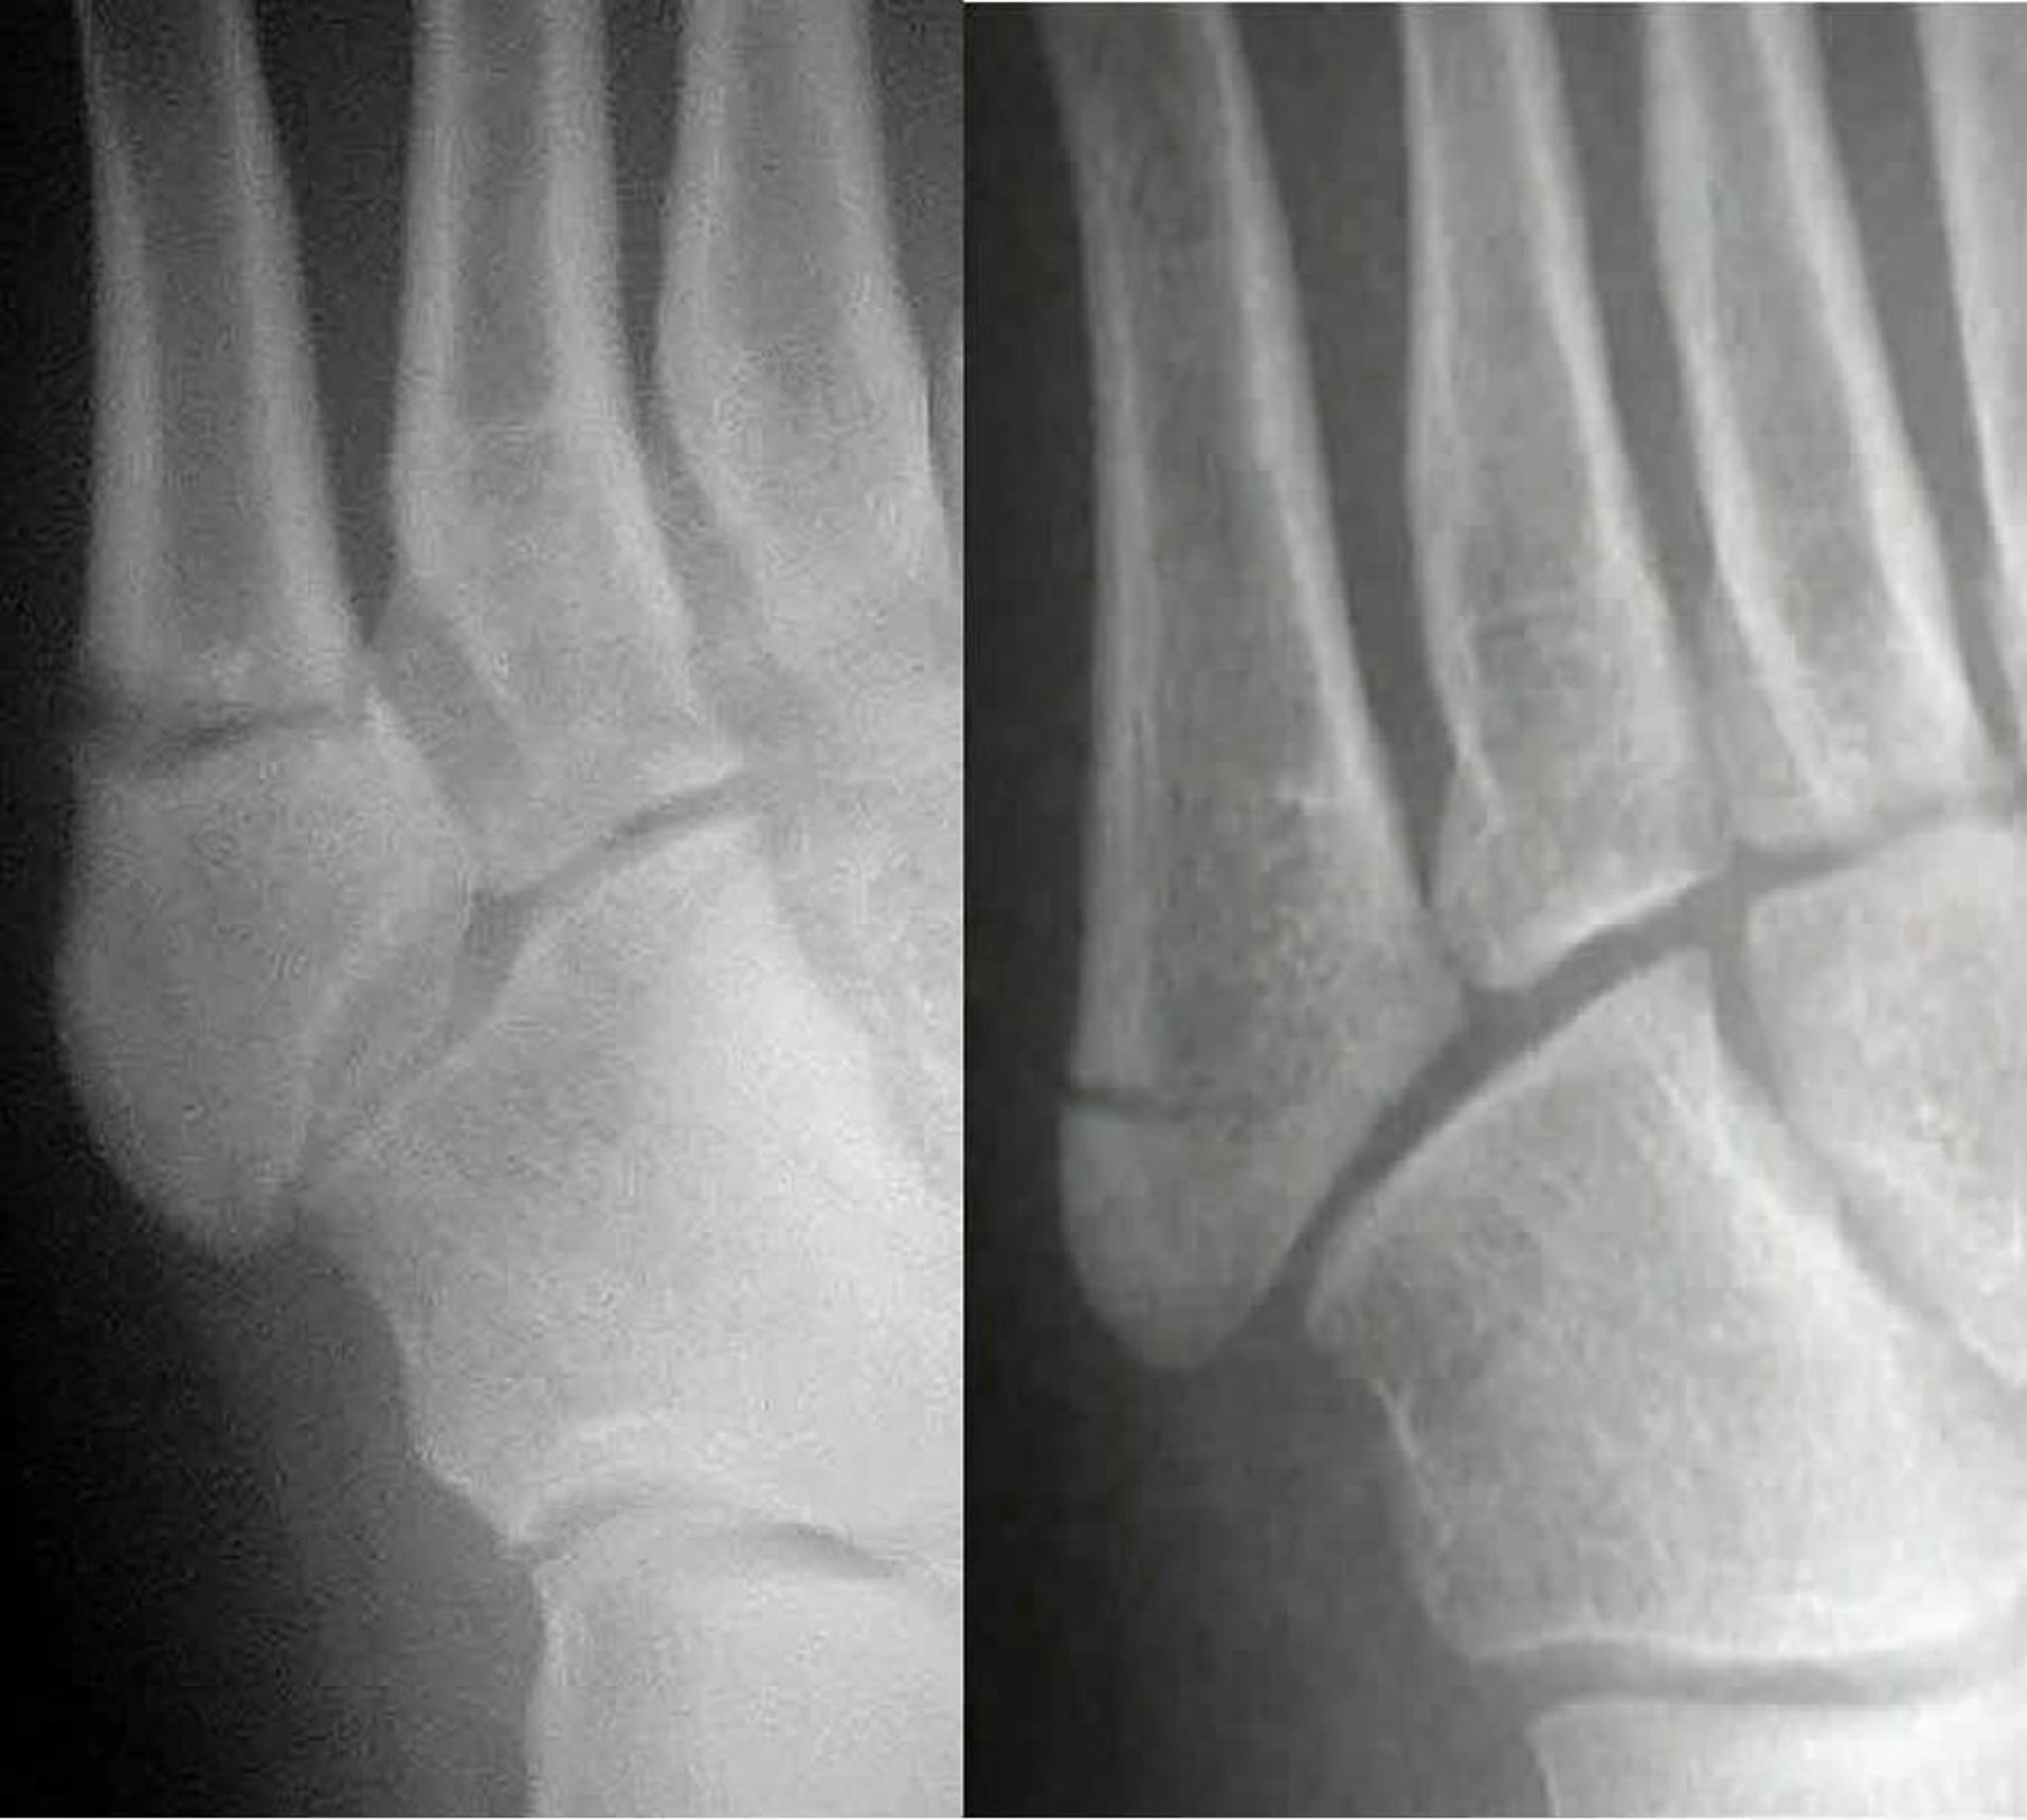

Jones骨折とpseudo-Jones骨折の比較

Jones骨折(左)では第5中足骨の骨幹部が骨折するが,pseudo-Jones骨折(右)では第5中足骨の基部が骨折する。治療法が異なるため,両者の鑑別が重要である。